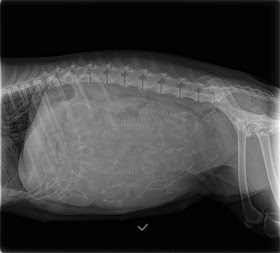

| If you click on the pic, it will enlarge. See those round circles attached to spines? Those are puppies! |